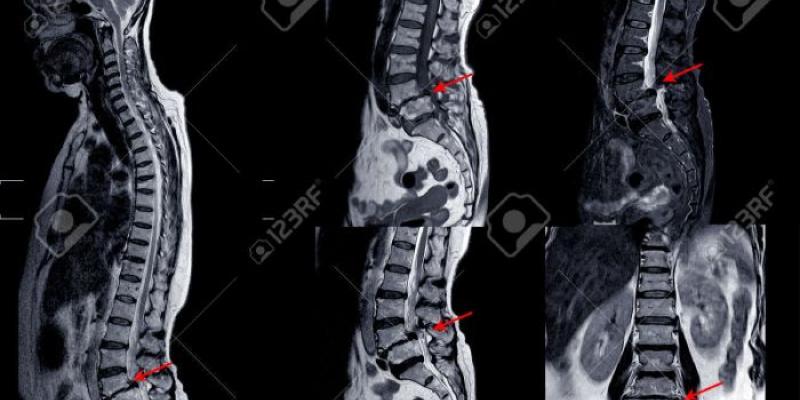

RNM de la columna lumbar que muestra una grave mielopatía medular